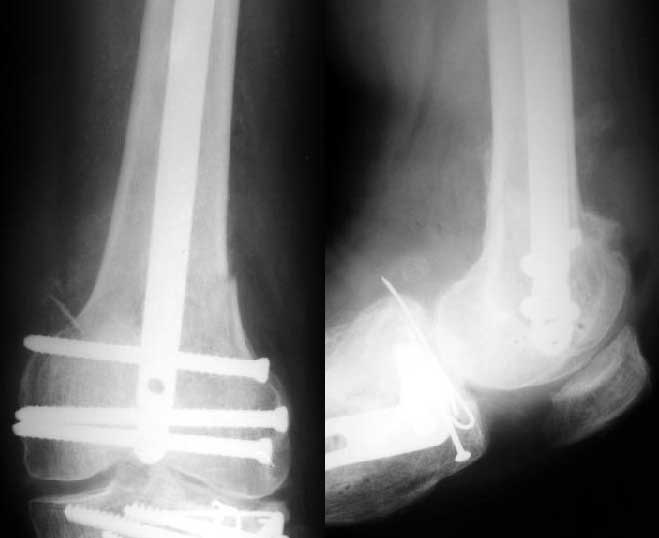

Отправитель: V. M. Iyer 01 Январь 2004, 15:17

1

2

The mobilisation of knee is started immediately from the second day. Weight bearing is permitted as in any other interlocked nailing. That is, Toe touch to start with and within four days, partial to in another two weeks, full weight bearing. Of course that is assuming that the correct size nail has been used. Up to 70 kg body weight, 11no will be good enough and 12mm if more.Usually at the 1st followup, at 6 weeks time, they have full flexion..I

have seen a few surgeons putting in a drain, but I have not found it unnecessary. There has never been any effusion needing active treatment.

Enclosing a recent intraop picture